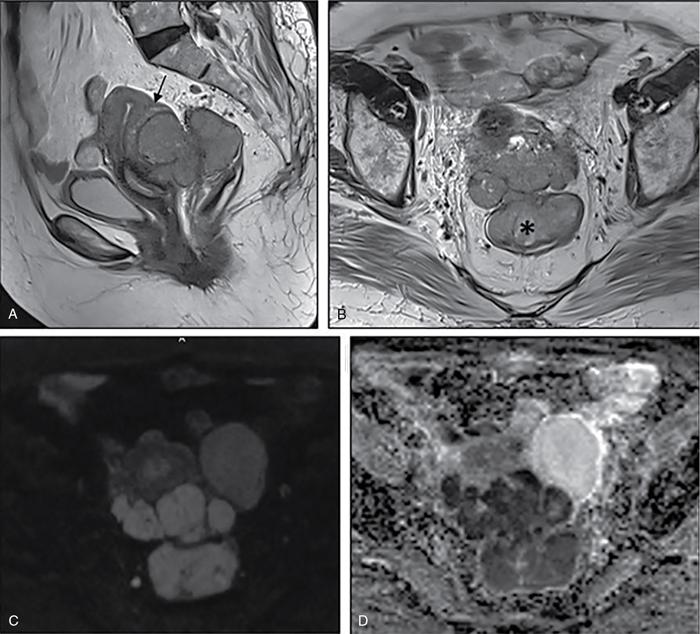

Suriyaprakash Nagarajan, Rupa Renganathan, Suhasini Balasubramaniam, Anupama Chandrasekharan, Kumarsampath Sumeena OVARIAN CYST VERSUS BLADDER Cystic lesions are common in female pelvis and mostly they originate from ovary. Ovarian cysts can arise from epithelial, stromal or germ cell components and can be benign or malignant cystic lesions. Pelvic Ultrasonography (USG) is the preferred imaging modality for evaluation of adnexal cystic lesions. Large simple ovarian cyst appears unilocular, anechoic with thin smooth walls. Such large simple cysts are confused with distended bladder. Distended bladder is a condition in which the urinary bladder is full and the patient is unable to void completely causing abdominal discomfort and pain. Distended bladder can be due to obstruction to passage of urine, neurological disorder or spastic sphincter. Differential diagnosis of cystic lesions in pelvis can be intraperitoneal, extraperitoneal and both intraperitoneal and extraperitoneal. Cystic lesions of intraperitoneal origin includes peritoneal inclusion cyst, paraovarian cyst, mucocele of appendix and hydrosalpinx. It is important to differentiate large simple ovarian cyst and distended bladder when patient presents with lower abdomen pain and the patient’s clinical history helps to make an accurate diagnosis (Table 11.4.1.1). UTERINE VERSUS EXTRAUTERINE MASS Ultrasound is usually the initial imaging modality for the pelvic mass. When USG findings are indeterminate to ascertain the organ of origin and to characterize, the next imaging modality is MRI due to its superior soft tissue resolution and multiplanar imaging capability (Figs. 11.4.2.1 and 11.4.2.2). Signs are demonstrated in Figs. 11.4.2.3 to 11.4.2.6. The sequences used in MRI pelvis are conventional T2WI in all three planes and T1WI in single plane. The problem-solving sequences are oblique coronal and oblique axial T2 along and perpendicular to the long axis of uterus in sagittal localizer. It can identify the organ of origin. Other sequences like T1 fat sat, diffusion-weighted imaging (DWI) and dynamic contrast T1WI with fat sat and subtracted images help to characterize the lesion further. BLADDER MASS VERSUS PROSTATE MASS Irregular mass lesions in the bladder neck are termed as ‘Bladder occupying lesions’. It is often difficult to determine whether the origin of these lesions is the bladder or the prostate gland. Transabdominal Ultrasound with colour Doppler studies and CT imaging do not usually delineate the origin of the lesions. The following features may aid in the differentiation (Table 11.4.3.1): History Painless haematuria Usually asymptomatic Investigations TAS, TRUS, MRI, Cystoscopy-guided biopsy PSA, DRE, TRUS, MRI, TRUS-guided biopsy At what point is the cross over between the two lesions T4 bladder cancer invading the prostate Aggressive prostate cancer protruding into the bladder Epicenter of the lesion Within the bladder Within the prostate gland Central necrosis in the mass Not commonly seen Seen in sarcomas IVU/CT urography Additional lesions in the urinary tract suggest that the bladder occupying mass in the bladder neck is of bladder-origin Prostate masses do not commonly cause masses in the urinary tract except for the very rare metastasis Virtual cystoscopy Additional lesions in the bladder wall and dome suggest that the bladder occupying mass in the bladder neck is of bladder-origin MRI T2 hypointensity Bladder masses are usually T2 hyperintense Seen in adenocarcinomas MRI T2 hyperintensity Bladder masses are usually T2 hyperintense Urothelial tumours infiltrating the prostate, neuroendocrine masses MRI T1 and T2 hyperintensity Bladder masses are usually T1 hypointense and T2 hyperintense Mucinous adenocarcinoma MRS Elevated choline values are seen in highly cellular masses Elevated choline:citrate ratio in prostate malignancies No significant finding in mucinous adenocarcinoma DWI Diffusion restriction is seen in malignant bladder masses No restriction in mucinous adenocarcinoma BPH versus bladder mass Exophytic BPH has signal intensities and appearance similar to and is contiguous with BPH within the gland OVARIAN MASS VERSUS PARAOVARIAN MASS Ultrasonography (USG) is the primary imaging modality in patients presenting with pelvic symptoms. Transvaginal, transabdominal or both should be performed in evaluation of such patients to differentiate ovarian and nonovarian origin of the lesions. Ovarian lesions can be a simple ovarian cyst, complex cyst with septations and solid components or a solid mass. Paraovarian lesions are remnants of the Wolffian duct in the mesosalpinx along fallopian tube or the ovaries and do not arise from the ovary. Paraovarian cysts are classified based on their site of origin into paratubal mesosalpingeal cysts, hydatid cysts of Morgagni, paraovarian cystadenoma and subserosal cysts. Differentiation of ovarian and paraovarian lesion poses significant diagnostic challenge. Both Computed tomography (CT) and Magnetic resonance imaging (MRI) are essential problem-solving tool in determining the site of origin of a pelvic mass. The first step in pelvic mass evaluation is to find out if it is ovarian or nonovarian in origin. Characterization of paraovarian or ovarian lesions is of utmost importance in order to optimize therapeutic procedures and it influences patients management (Figs. 11.4.4.1 and 11.4.4.2). Findings such as ovarian vascular pedicle sign, claw sign, bird beak sign and visualization of normal ovary helps to differentiate between ovarian and paraovarian lesions. Subsequently ovarian lesions should be categorized into benign, indeterminate and malignant masses (Table 11.4.4.1).

Ipsilateral ovary not seen separately from the lesion (Phantom sign) or the cyst is seen to arise from within the ovary (embedded organ sign).

Complete or incomplete septae often seen (Fig. 11.4.1.2A).

Ovarian cysts are anechoic lesions noted on one side of pelvis (Fig. 11.4.1.2B). Normal ovarian stroma can be seen around the cysts in case of small cysts.

Colour Doppler shows vascularity in the septum (Fig. 11.4.1.2C).

Solid components more commonly seen (Fig. 11.4.1.2D).